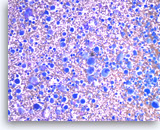

Metastatic renal cell carcinoma,

Pancreas FNA, Direct Smear.

The aspirates show large three-dimensional clusters of malignant epithelial cells in a bloody background. The tumor cells have vacuolated cytoplasm.

20X

Metastatic renal cell carcinoma,

Pancreas FNA, Direct Smear.

The aspirates show large three-dimensional clusters of malignant epithelial cells in a bloody background. The tumor cells have vacuolated cytoplasm.

20X